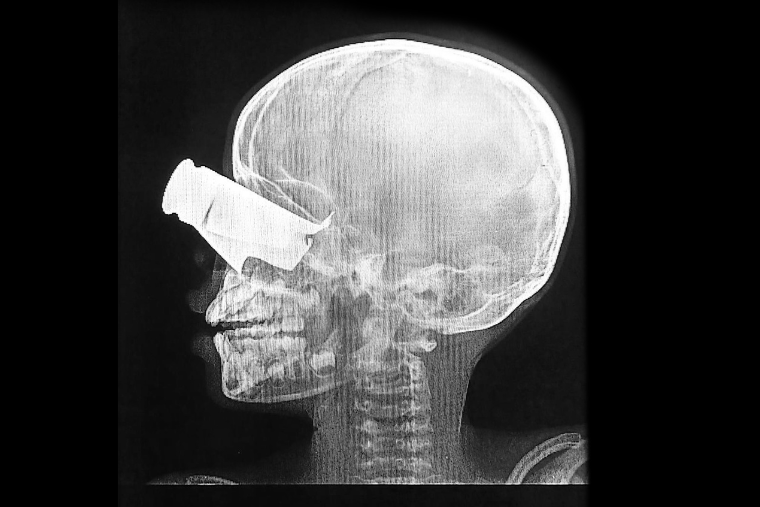

隣国・チャドの町ティネでは2月以降、国境なき医師団(MSF)とチャド保健省が連携し、ドローン攻撃で負傷した457人を治療してきた。

病院ではこれまでに計38人が死亡した。このうち19人は、国境地帯が攻撃を受けた3月16日のわずか一日だけで亡くなった人びとだった。

この2カ月の間に、私たちはチャド保健当局と連携して457人を治療しました。負傷者の中には子どもも6人いました。けがのおよそ半数は腕や脚に集中しており、開放骨折も少なくありません。これほど多くの重傷患者が一度に運ばれるとは予想していませんでしたが、私たちはできる限り患者の容体を安定させ、傷の手当てをして、命を守るための手術をしました。